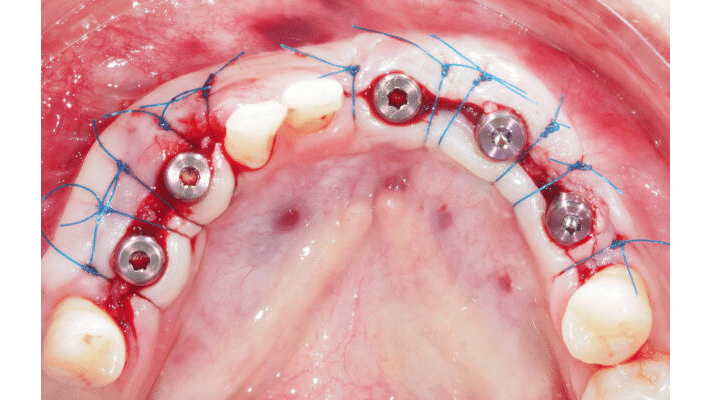

Étape 1 : Le lit receveur (Fig.1 à 4)

Il est primordial de créer une étendue désépithélialisée la plus superficielle possible afin de laisser une épaisseur sous-jacente à coloniser suffisamment importante. Les cellules kératinisées vont proliférer sur cette surface périostée et recréer le nouvel environnement péri-implantaire.

Cette désépithélialisation se fait tangentiellement, en épaisseur partielle à la lame froide, bien au-delà de la zone où la bandelette sera positionnée. Les limites de la zone régénérée doivent impérativement être bordées de tissu kératinisé (Fig.3).

– Astuce n°1 : Ne pas hésiter à couper aux ciseaux l’excédent de muqueuse résiduel laissé dans le lambeau avant de le suturer au périoste (Fig.3).

– Astuce n°2 : Suturer l’extrémité distale du lambeau en tension distale et l’extrémité mésiale en tension mésiale. La résultante est un plaquage horizontal vertical du lambeau. Finaliser par une suture continue (surjet croisé) de l’extrémité du lambeau au périoste (Fig.4). Un fil tressé à résorption rapide est conseillé.

– Astuce n°3 : Réaliser, perpendiculairement, une incision horizontale jusqu’au contact osseux afin de sectionner les fibres musculaires sous-jacentes.